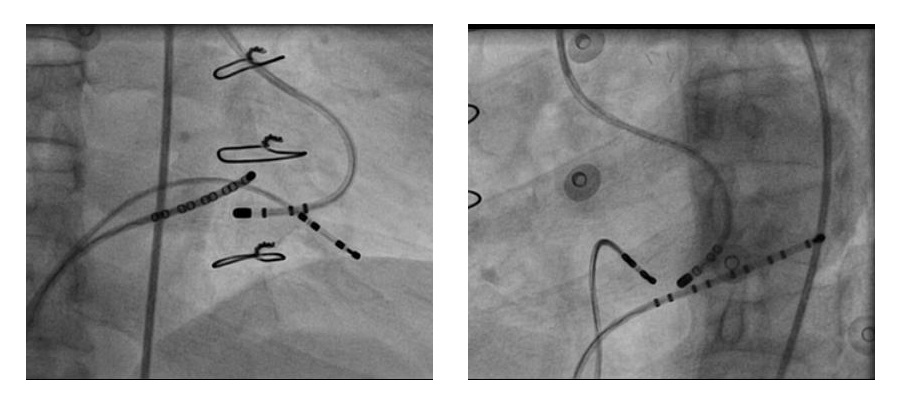

Mapping approaches - Rhythm

Mapping approaches

• Earliest ventricular activation during maximum preexcitation with atrial pacing *

• Earliest atrial activation during ventricular pacing *

• Earliest atrial activation during orthodromic reentrant tachycardia

• Intermediate preexcitation during sinus rhythm / slow pacing

(*) May not recognise AV conduction injury

Septal pathways - Ablate during tachycardia

asap_ablation_tachy.jpg

Left sided pathways - Entrain and ablate

entrain_ablate.jpg